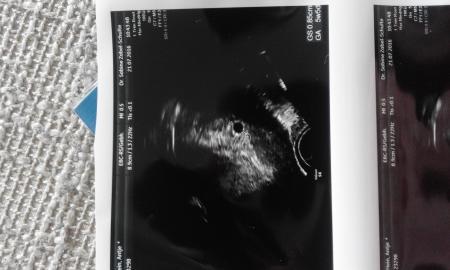

Hallo. Bin zurück. Alles war soweit in Ordnung. Laut US. Fruchthöhle 5+5 passt zum verschobenen ES. ET hat sie nun den 18.3. Gemeint. Und zu sehen war auch nur eine. Puuuh haha. Könnte so viel sein. Hämatom oder es war ne zweite FH . Oder so meint sie der schnelle Wachstum der Gebärmutter. Nehme 2x Utro und etwas schonen. Ich versuche mal ein Bild später hoch zu laden

Gott sei dank. Sonntag konnte man das Nu erahnen und 4 Tage später sah ich sie sofort und war messbar ![]()